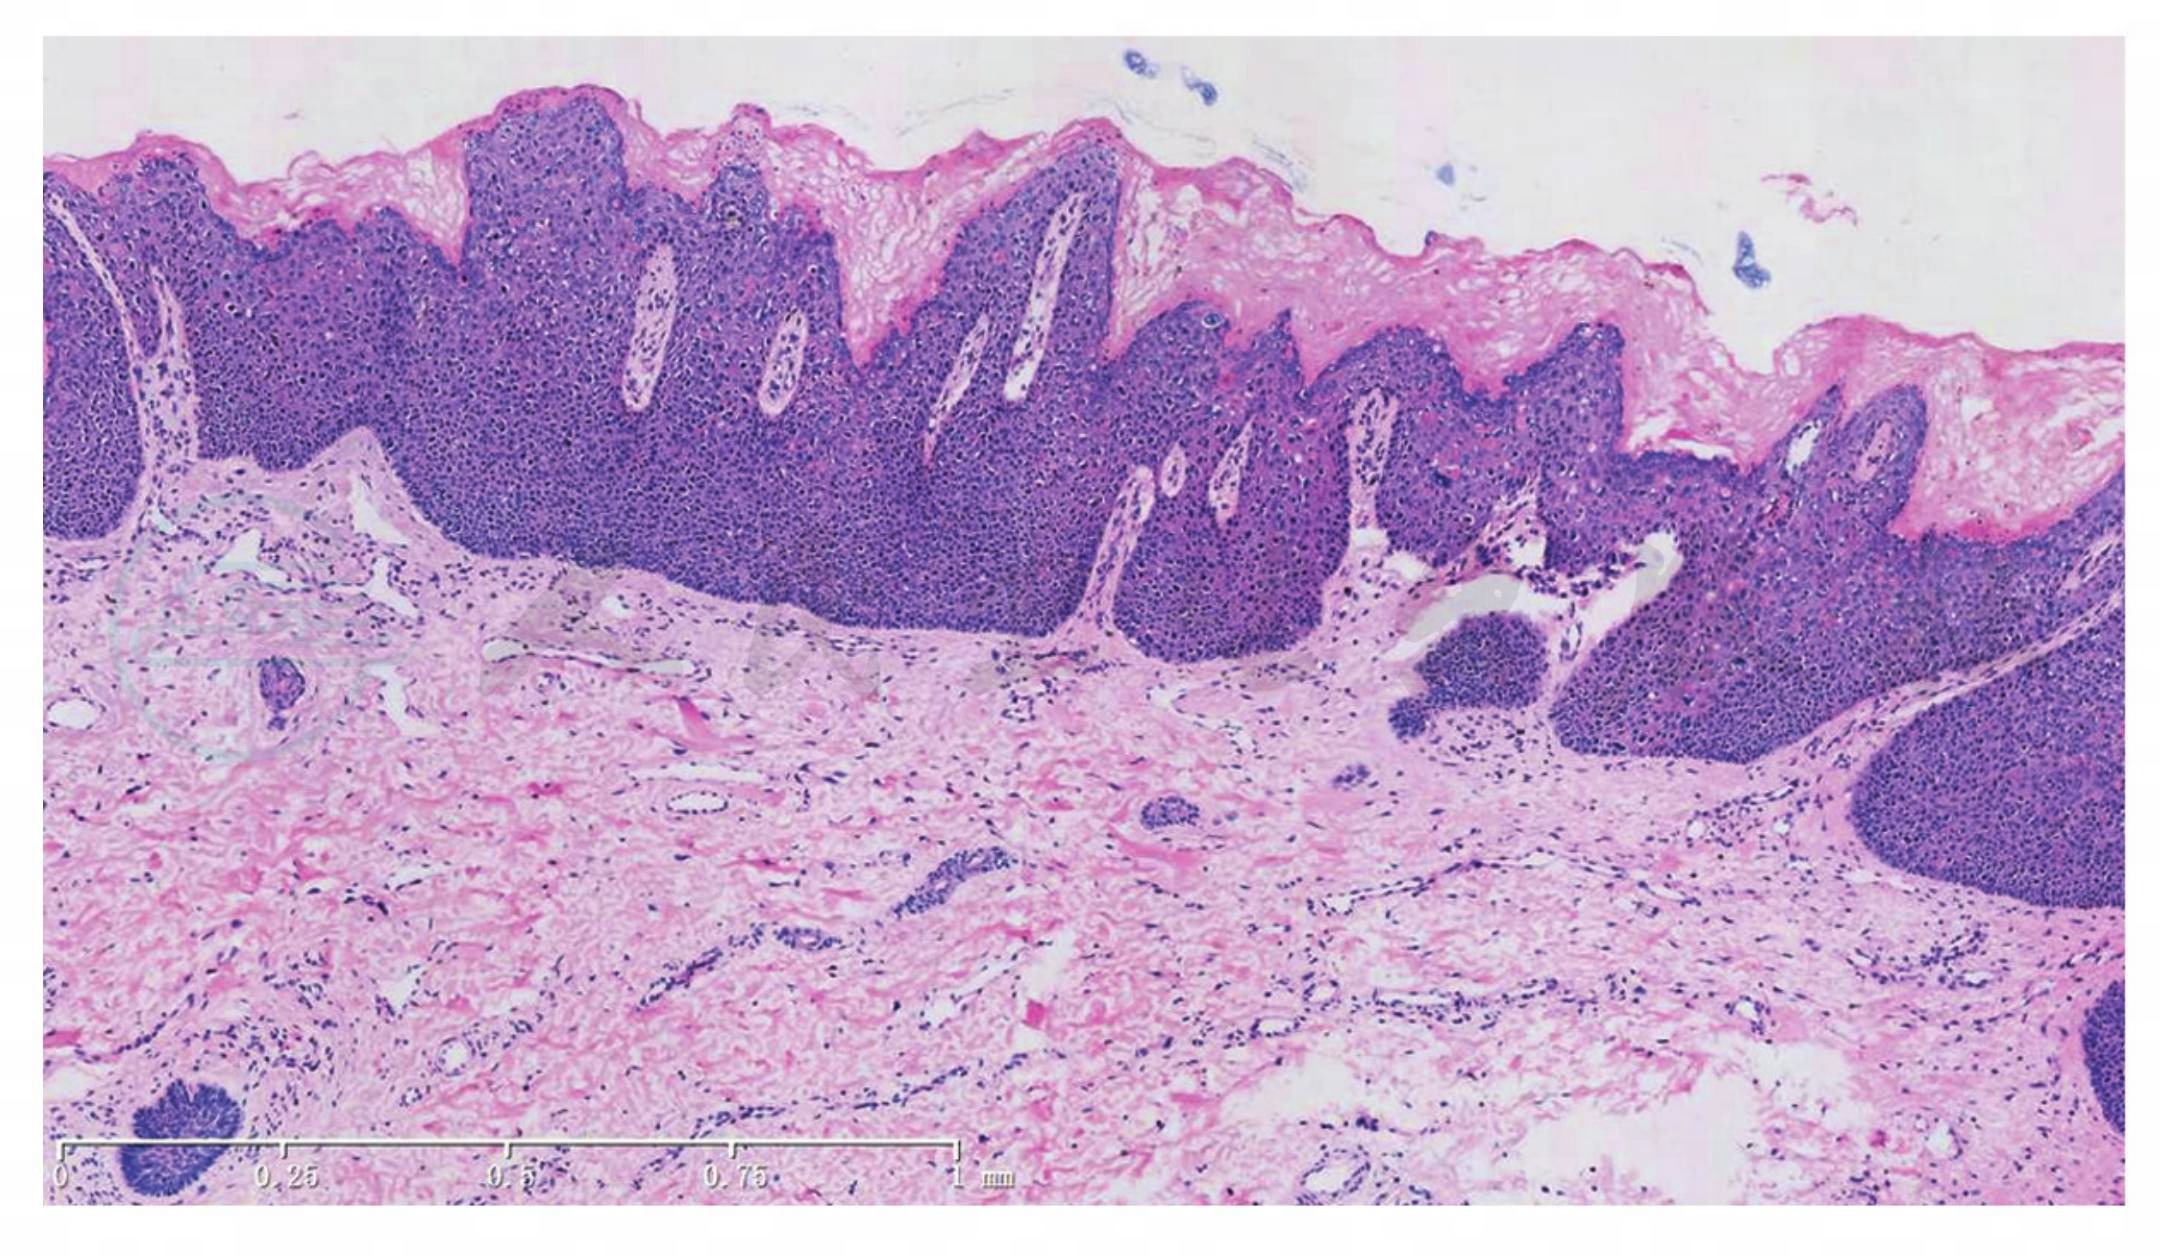

组织学呈原位癌表现:电镜可见角质细胞中病毒颗粒;癌前病变表现为没有明显界限的连续的形态学改变;角化细胞层的不正常分化;核质比例的增大、胞核大小不一和有丝分裂象数目增加,后者包括不正常有丝分裂和深染(图1,图2)。

图1鲍恩样丘疹病。表皮乳头瘤样增生,棘层增厚,细胞排列紊乱(HE染色,×100)